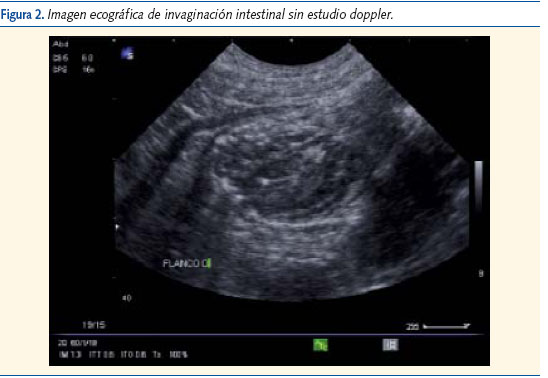

Evolución: durante su observación en urgencias presenta 4 vómitos y tendencia al sueño; se mantiene afebril en todo momento. Se le realiza una ecografía abdominal (figuras 1, 2 y 3) en la que se observa una invaginación ileo-ileal y es remitido al servicio de cirugía pediátrica del hospital de referencia, donde se repite la ecografía. No se encuentran entonces signos de dicha invaginación pero sí varias adenopatías mesentéricas. El paciente permaneció en observación 24 horas y fue dado de alta sin complicaciones.

De forma clásica, se considera que el gold standard para el diagnóstico es el enema opaco, si bien la ecografía abdominal ha desplazado a éste por ser menos invasiva2.